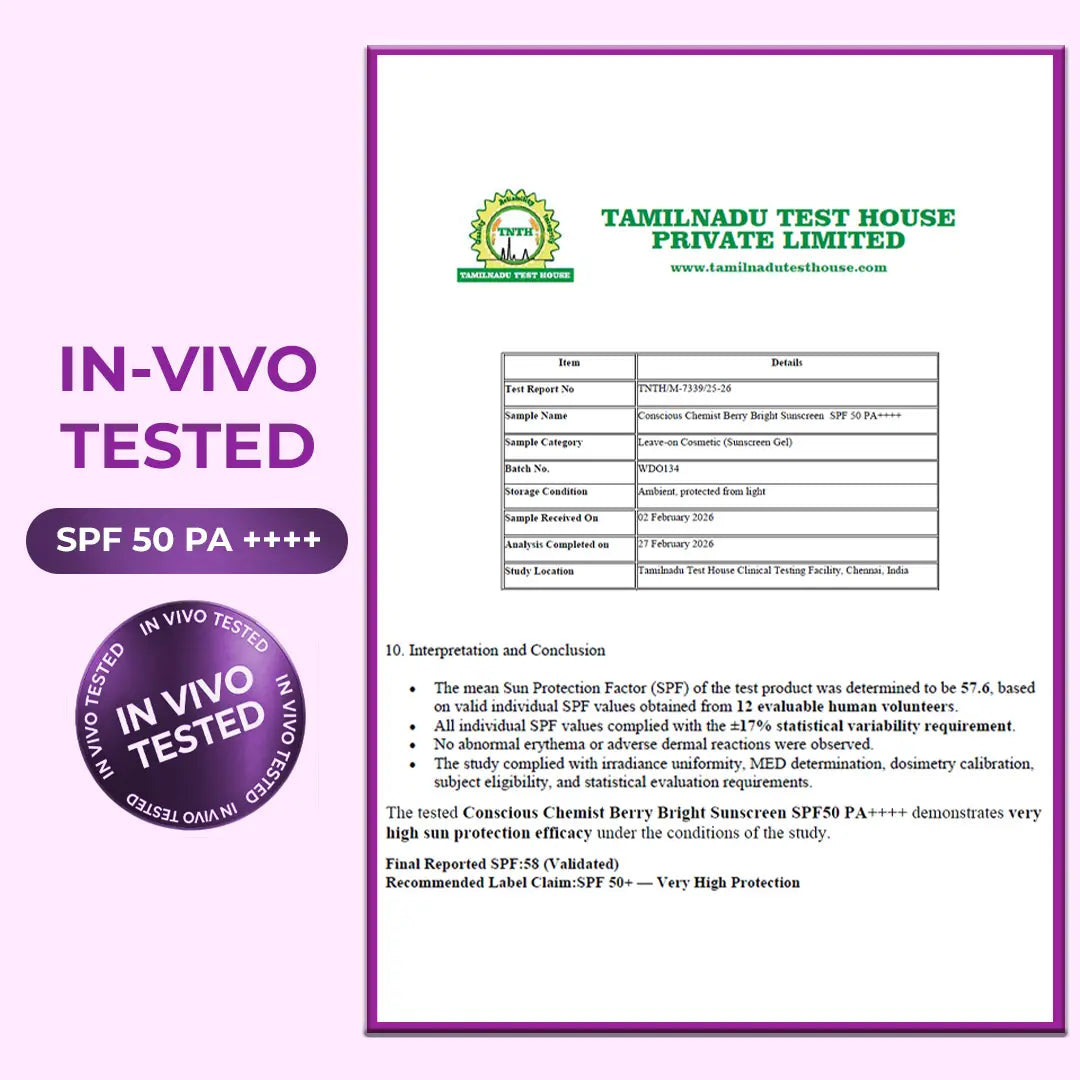

SPF 65 PA++++